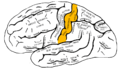

Lateral surface of left cerebral hemisphere, viewed from the side.

Lateral surface of left cerebral hemisphere, viewed from the side. Drawing to illustrate the relations of the brain to the skull.